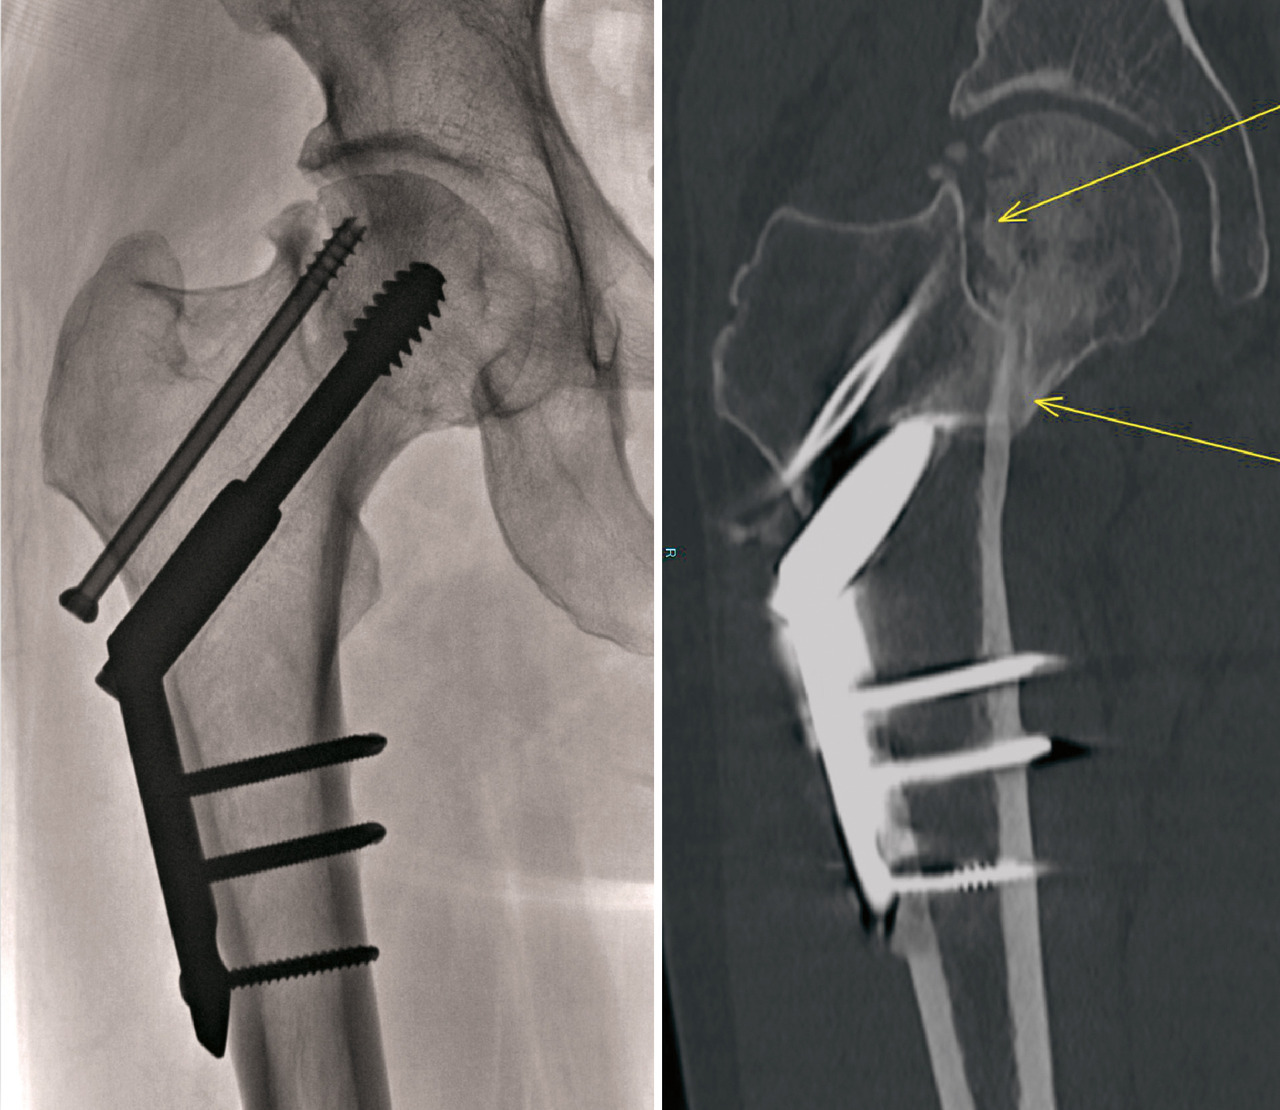

En cas de fracture du massif trochantérien, compte tenu du faible risque de nécrose, la solution chirurgicale est presque toujours l’ostéosynthèse. Cette dernière a pour but de fixer la fracture une fois la réduction de celle-ci obtenue. Il peut s’agir d’une vis-plaque ou d’un clou fémoral proximal verrouillé type clou gamma (fig. 15). Dans les cas de fracture particulièrement instable ou lorsque la fracture s’étend vers la diaphyse, l’ostéosynthèse par clou est recommandée.

La faillite mécanique de l’ostéosynthèse (fig. 16) : c’est la complication la plus fréquente des ostéosynthèses (de 4 à 12 %). Elle peut être liée à un défaut dans la réalisation de l’ostéosynthèse mais aussi à un os de piètre qualité ou une reprise intempestive de l’appui.

La pseudarthrose (fig. 19) : c’est une complication qui concerne plus particulièrement les fractures cervicales vraies, en cas d’ostéosynthèse, mais aussi parfois les fractures du massif trochantérien. On parle de pseudarthrose si la fracture n’est pas consolidée au bout de 6 mois et de retard de consolidation entre 3 et 6 mois. En général, il s’agit de douleurs persistantes, parfois d’une modification du montage. Lorsque le diagnostic n’apparaît pas certain, il est indiqué de réaliser un scanner. Le traitement en est une prothèse chez les personnes âgées et une ostéotomie de valgisation chez les patients jeunes.